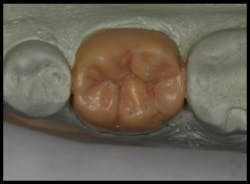

Given how difficult the handling properties of many glass ionomers can be, there are many challenges to restoring proper contour and function. We decided that another solution was necessary. A direct restoration using a glass hybrid restorative material in a guided matrix was used. A diagnostic wax-up was completed (figure 3).

Figure 3: A diagnostic wax-up was completed.